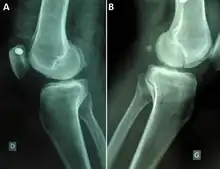

| Medio-lateralradiographsof knees joint showing a bilateral Hoffa fracture of the medial femoral condyle and fracture suspicion of left tibia plateau. (A) right knee; (B) left knee.[1] |

A Hoffa fracture is an intra-articular supracondylar distal femoral fracture, characterized by a fracture in the coronal plane.[1]